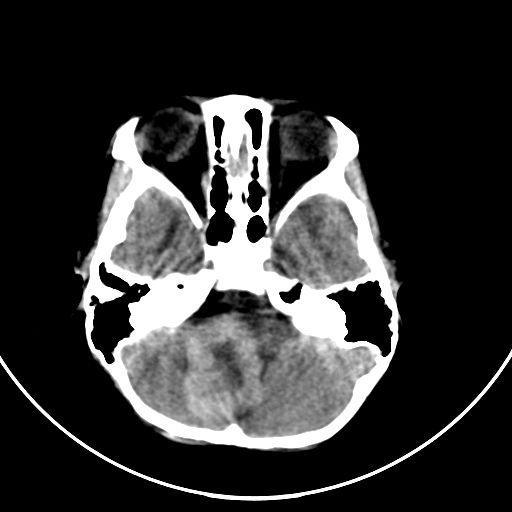

以下是引用zjzjr在2008-7-27 9:56:00的发言:[br]考虑髓母细胞瘤伴梗阻性脑积水.建议增强或mri

以下是引用子十在2008-7-27 9:53:00的发言:[br]考虑髓母细胞瘤